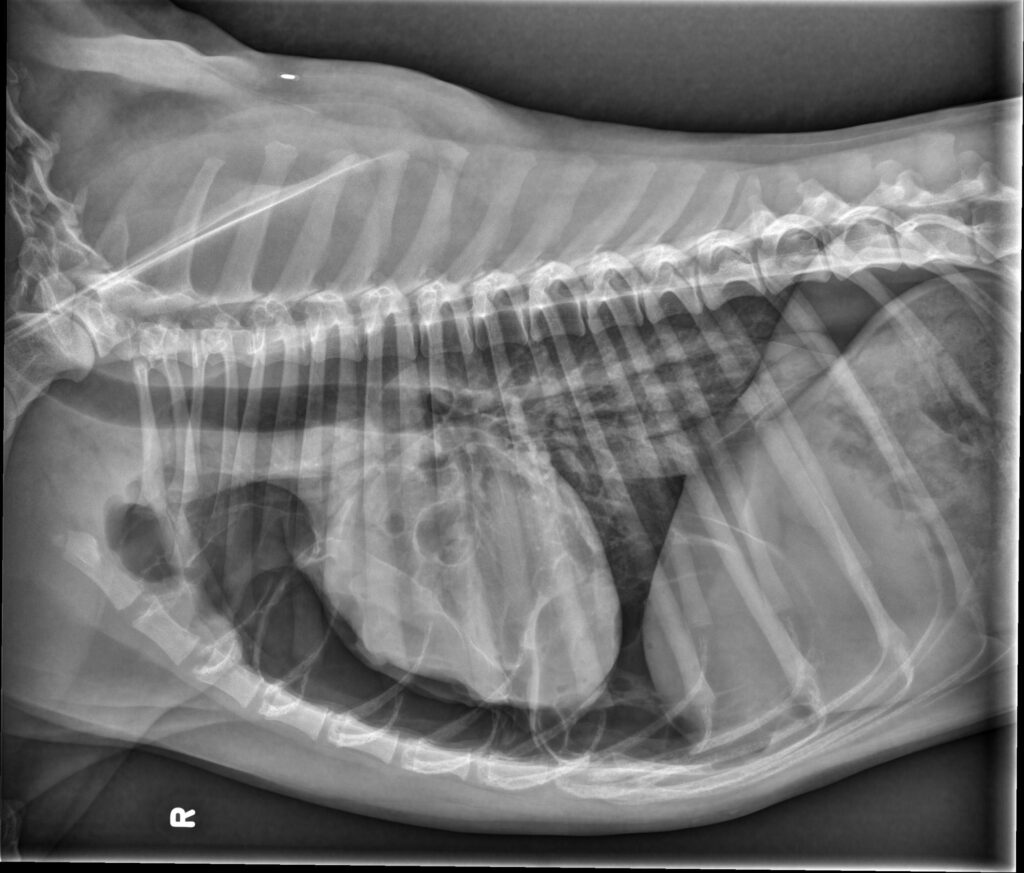

Radiology Quiz June 2025

History 10 year old female cat. Presented for anemia.